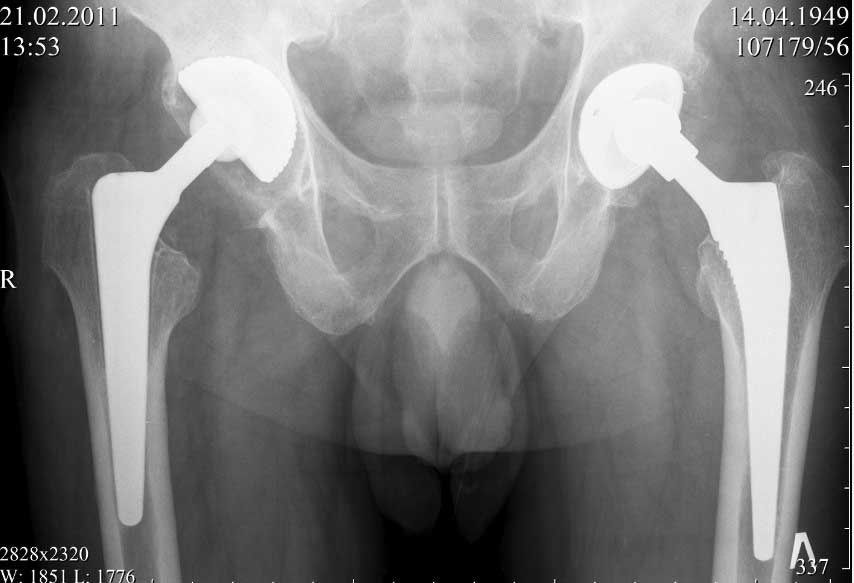

Если не ошибаюсь, то у больной имеется нестабильность бедренного компонента эндопротеза. Стартовые ("помповые") боли, а также зона просветления вокруг цемента и смещение цемента относительно кости...

Здравствуйте! К сожалению, качество рентгенснимков очень низкое,трудно определить есть ли разряжение на границе цементная мантия-кость.

Здравствуйте. Несомненно качество снимков не позволяет определить зону демаркации (если она есть). Делать нагрузочные снимки не вижу смысла, так как объем миграции может мыть незначительным и "на глаз" не определяться. При наличие же значимой (видимой) нестабильности всегда будет выраженная зона демаркации кость-цемент. Имеет смысл сравнить снимки сразу после имплантации и на данный момент. Обнаруженная миграция ножки может быть косвенным признаком возможной нестабильности. Впрочем, насколько я знаю, допускается некоторое "проседание" ножки при безцементом и цементом протезирование с отсутствием болевого синдрома (по типу вторичной фиксации). А вот миграция+боль, почти всегда= нестабильность.

прилагаю рентген снимки сразу после операции в 2009г и февраль 2011г.